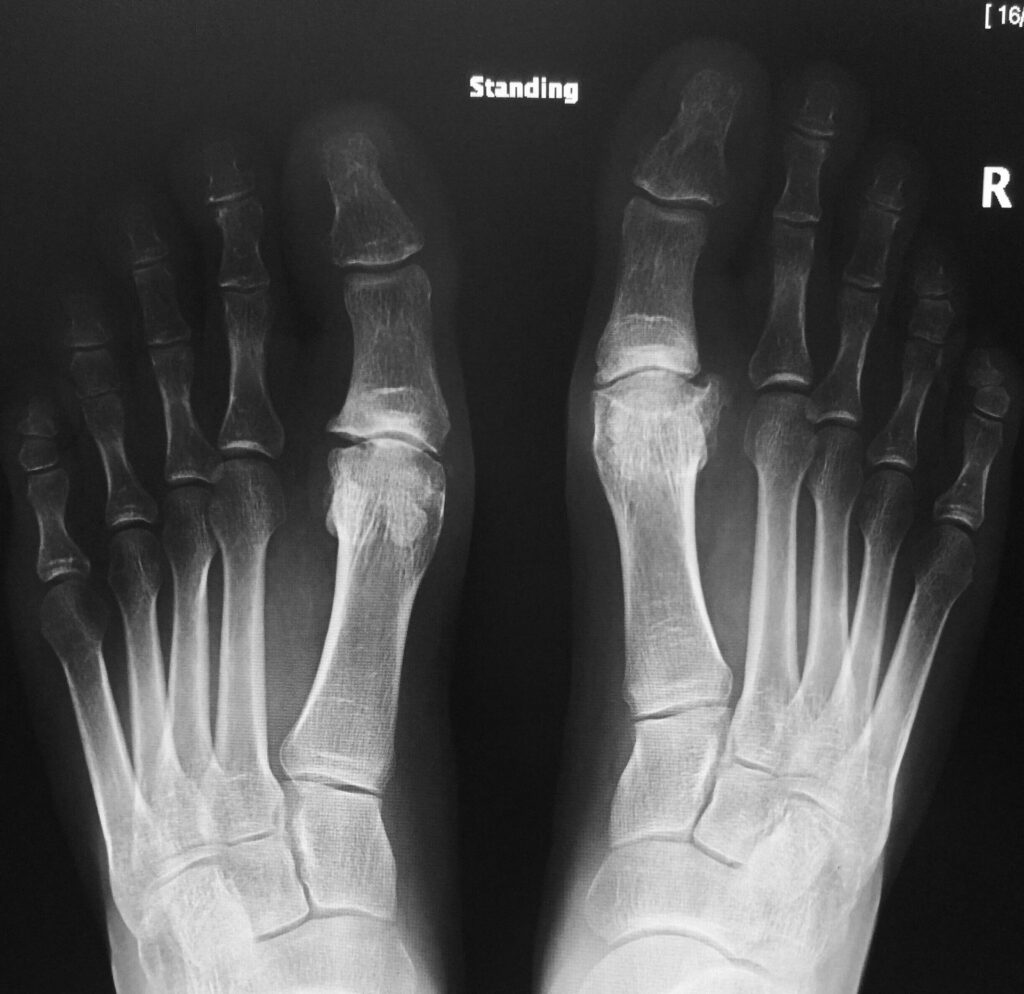

Udfordringerne ved Traditionel Diagnostik: Vægtbærende Røntgen

I årtier har vægtbærende almindelige røntgenbilleder været den primære metode til at diagnosticere knogle- og ledproblemer i foden. 'Vægtbærende' betyder, at billederne tages, mens patienten står op, så lægen kan se, hvordan knoglerne og leddene opfører sig under kroppens vægt. Dette er især vigtigt i foden, da mange problemer kun bliver tydelige under belastning.

Baseret på den kliniske mistanke vil det første skridt i billeddiagnostikken næsten altid være et vægtbærende røntgenbillede. Det er hurtigt, billigt og let tilgængeligt. I mange tilfælde, især hvis artrosen er fremskreden, kan røntgenbilledet være tilstrækkeligt til at bekræfte diagnosen.

- Når vi står og går, presser vores kropsvægt knoglerne i foden sammen. Dette afslører problemer som ledinstabilitet eller en indsnævring af ledspalten, som måske ikke er synlige, når foden er ubelastet (f.eks. liggende). Vægtbærende billeder giver et mere funktionelt og realistisk billede af fodens tilstand.